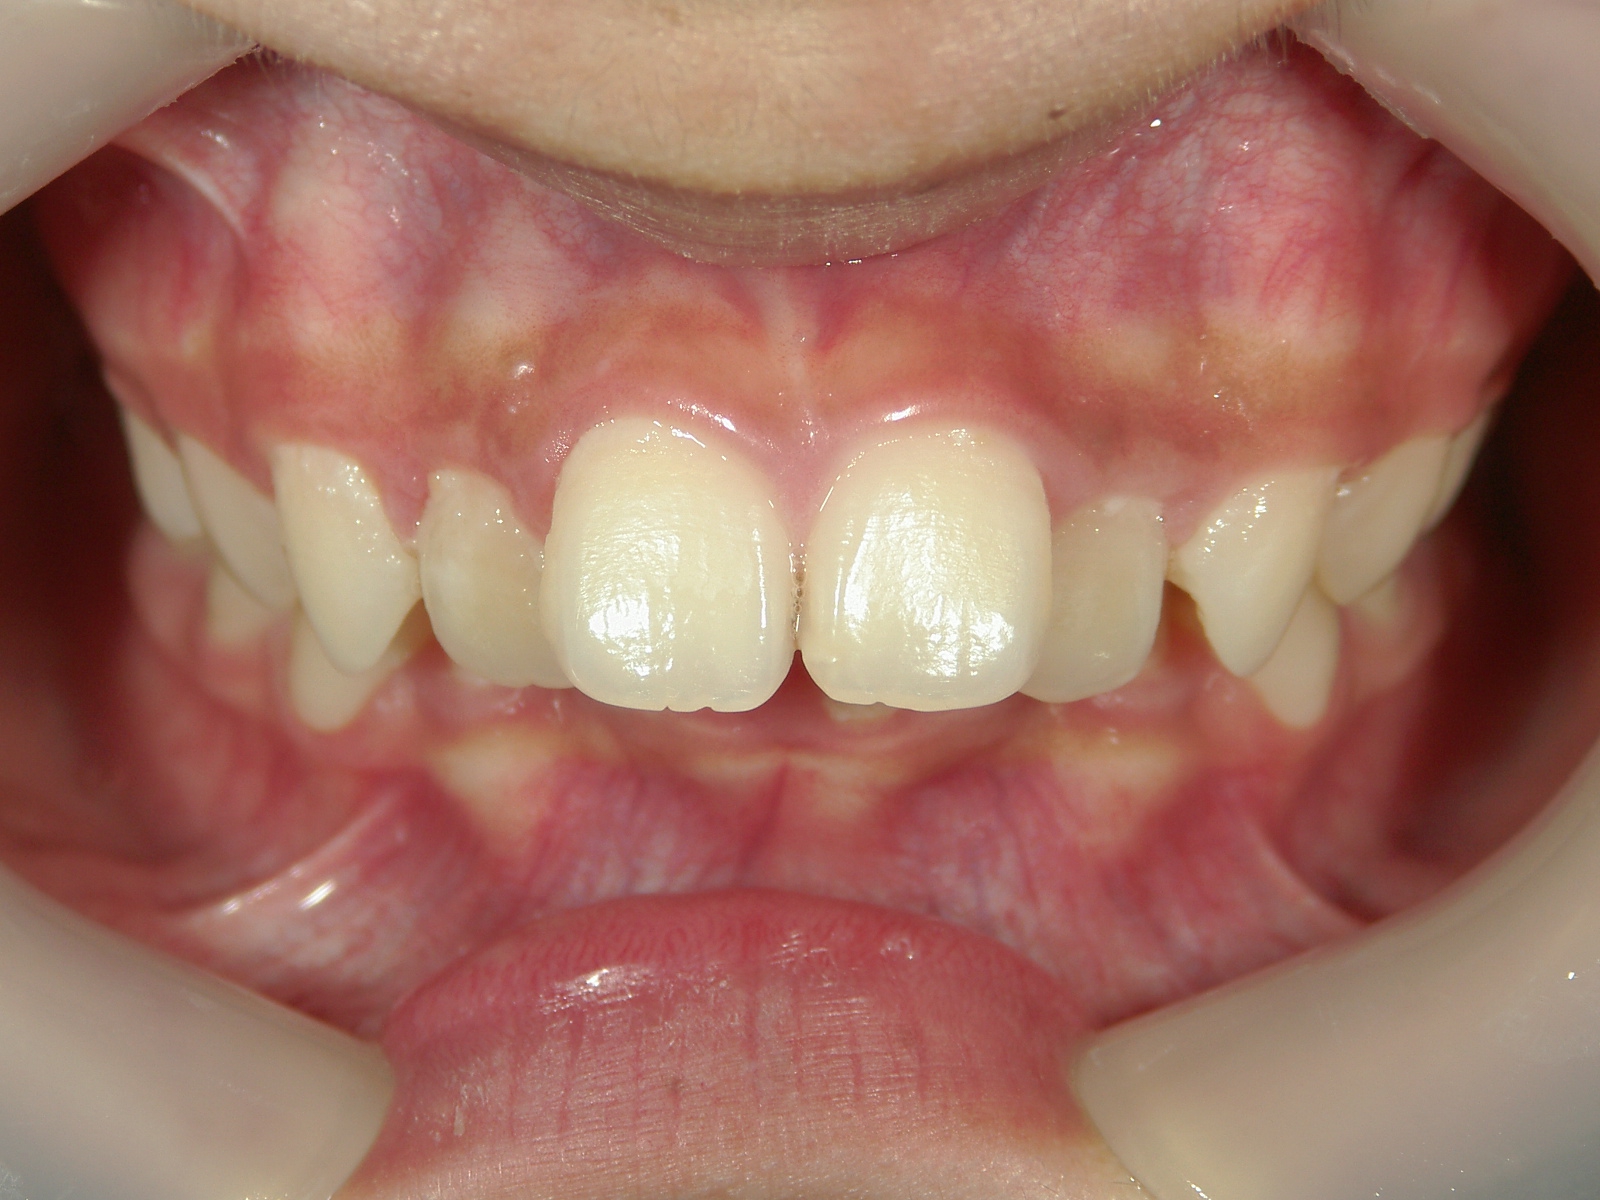

矯正歯科 治療後矯正歯科 全顎ワイヤー矯正 治療後矯正歯科(全顎ワイヤー矯正)治療後

矯正歯科 治療後

no.18_2196_治療後_右.jpgno.18_2196_治療後_正面.jpgno.18_2196_治療後_左.jpg